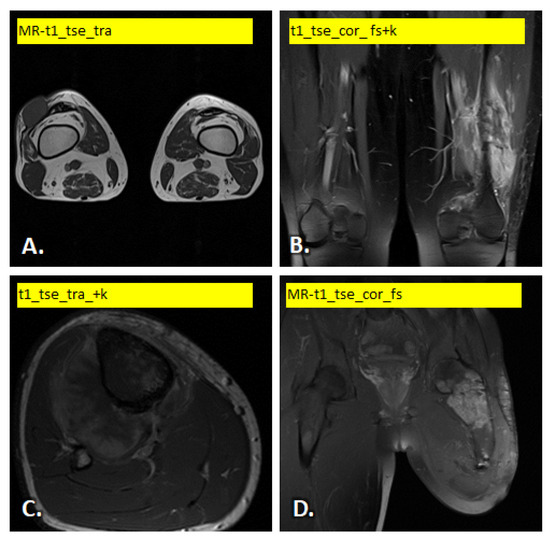

In Figure 1 and Figure 2 illustrate examples of the different images used.

Figure 1. Example of T1-weighted MRI scan variants: (A) soft tissue tumor in the lateral joint capsule of the right knee, (B) bone tumor (Ewing) in the lower end of the left femur, (C) bone tumor on the proximal posterior side of the right tibia and (D) bone tumor in the trochanteric area of the left femur.